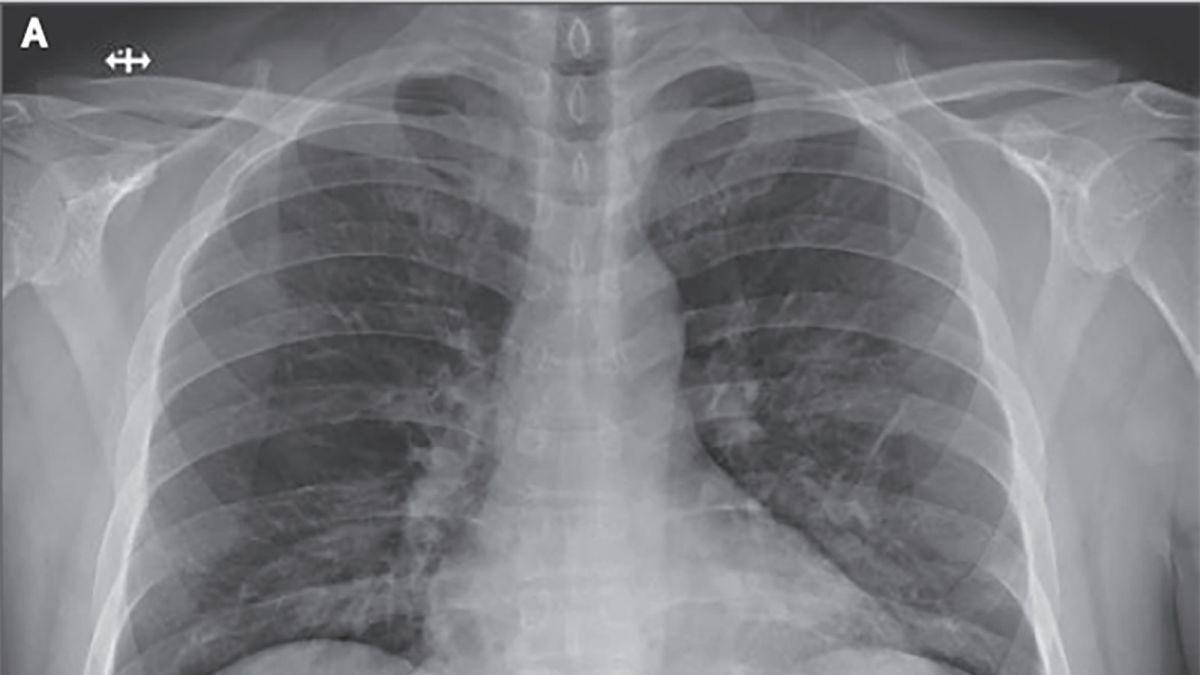

Tras realizarle una tomografía en el tórax, los médicos descubrieron que tenía un quiste enorme en el pulmón izquierdo, debido a un parásito llamado 'Echinococcus granulosus'.

Los expertos dieron a conocer que la mujer, de 75 años, tenía un quiste en el pulmón que se trasmite por parásitos en los perros.

Al identificar las causas del dolor, los médicos tuvieron que realizarle una cirugía de pulmón en la que se le logró sacar todo el quiste hidatídico, y la cual duró dos horas.